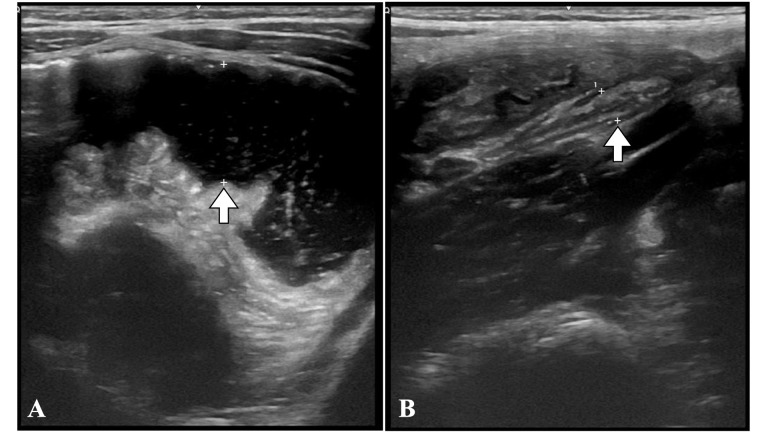

Heart failure (HF) is a clinical syndrome with symptoms and/or signs caused by structural and/or functional cardiac abnormalities. After discharge, patients with acute heart failure (AHF) face a significant risk of rehospitalization and mortality. Detection of residual congestion is crucial to reduce readmissions, improve prognosis, and decrease mortality. Echocardiography provides critical information about the severity of left ventricular dysfunction, elevated filling pressures, valvular dysfunction, and estimation of pulmonary artery systolic pressure. The VExUS approach integrates ultrasound evaluation of the inferior vena cava, hepatic veins, portal vein, and renal veins, providing valuable information about systemic congestion. Lung ultrasound detects pulmonary congestion, facilitating early intervention to prevent progression and hospitalizations. Ultrasound evaluation of the internal jugular vein and femoral vein complements the evaluation of venous congestion. Distension of the internal jugular vein during the Valsalva maneuver or the relationship between the diameter of the internal jugular vein and the femoral vein can predict adverse outcomes in patients with HF. In conclusion, a comprehensive ultrasound approach is crucial in the management of patients with critically ill heart failure. Multiparameter ultrasound evaluation provides vital information, guiding appropriate therapeutic interventions and avoiding potentially harmful measures.